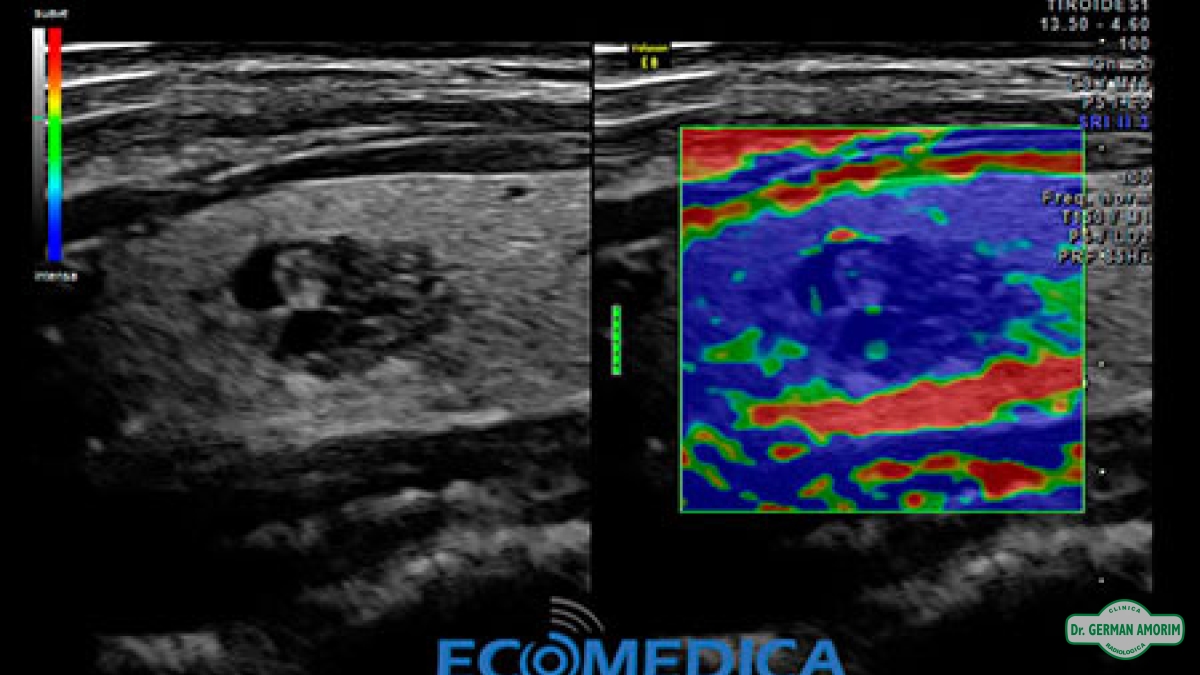

La elastografía es un método de diagnóstico complementario que utiliza los ultrasonidos para valorar la elasticidad o dureza de un segmento de un órgano o de un nódulo en estudio, mediante la tensión y compresibilidad que producen las ondas ultrasónicas en los tejidos del organismo en tiempo real.

Desde su invención, se han descrito múltiples aplicaciones en el estudio de los tejidos de la mama, próstata, tiroides y vasos sanguíneos.